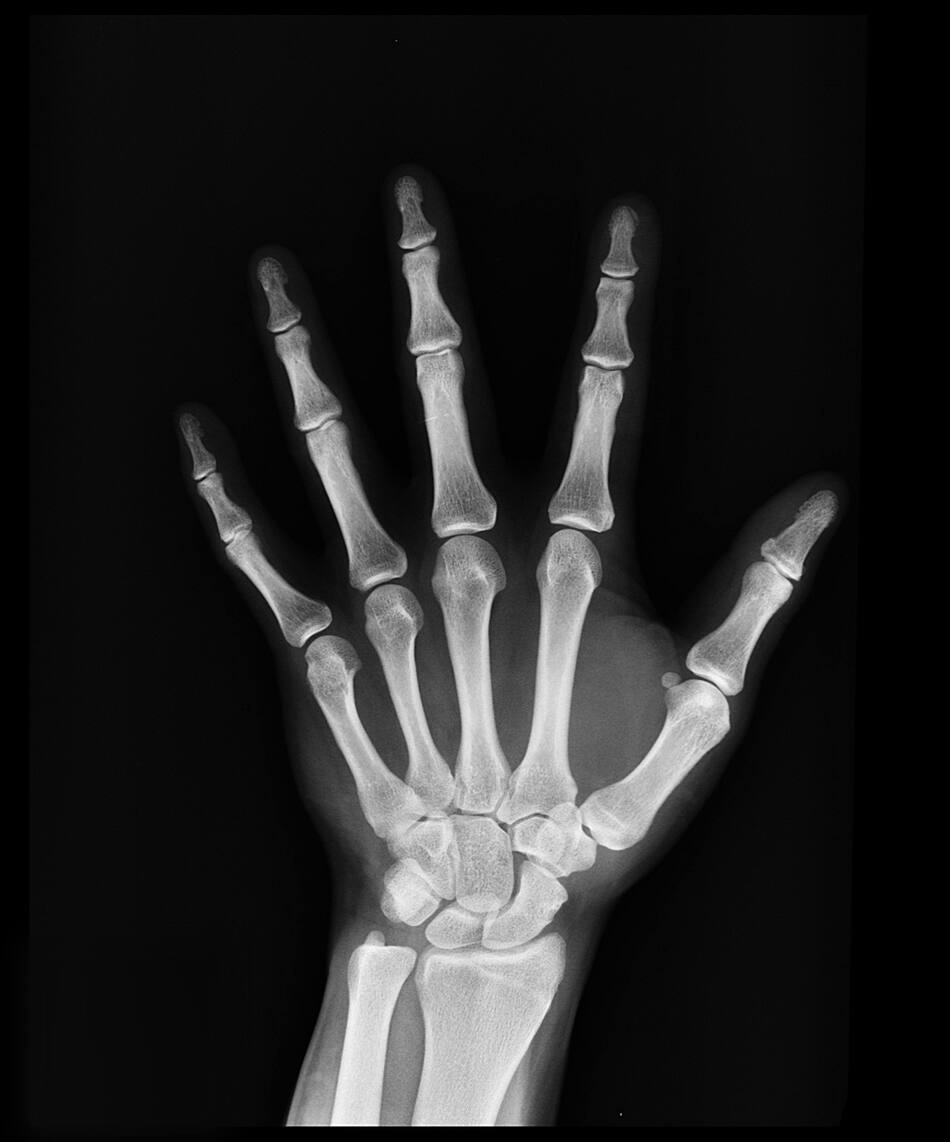

Los huesos necesitan mucho más que calcio para estar sanos. Foto: Unsplash

Huesos. Fuente: Pexels